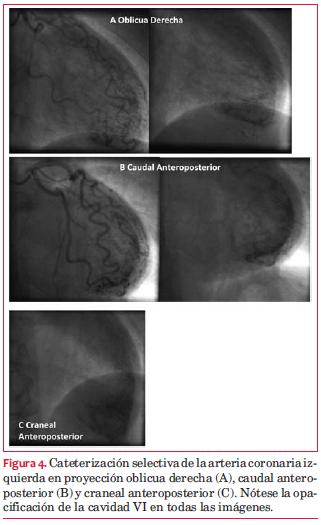

Por presentar una PEG de alto riesgo se consideró que el estudio no permitía descartar que el paciente presentara una patología de tres vasos con isquemia balanceada. Se decide realizar cineangiocoronariografía (CACG) de coordinación que informa ausencia de lesiones coronarias obstructivas significativas, observándose pequeñas fístulas arteriolo-ventriculares desde los ramos de la coronaria izquierda (figura 4).

Comentario

Presentamos el caso de un paciente asintomático con ECG compatible con isquemia durante la prueba de esfuerzo. Sin embargo, el centellograma no evidenció áreas de isquemia, aunque no la descarta completamente, ya que puede ocurrir que se trate de un fenómeno de isquemia balanceada. Se decide ahondar en el diagnóstico realizando un estudio angiográfico, el cual no muestra alteraciones de los vasos epicárdicos, aunque sí hace evidente la presencia de microfístulas hacia la cavidad ventricular izquierda.

Aunque no se mencionan en las publicaciones de Angelini, una entidad poco frecuente son las microfístulas hacia el VI, pequeñas fístulas que drenan a la cavidad ventricular izquierda. Su prevalencia es desconocida. De la base de datos de la Dutch Survey of coronary artery fistulas en la población adulta, de 71 pacientes con fístulas, 20 eran portadores de microfístulas múltiples desde las coronarias al VI(17). El diagnóstico se realiza mediante angiografía, observando la rápida opacificación de la cavidad del VI a través de las fístulas(19).